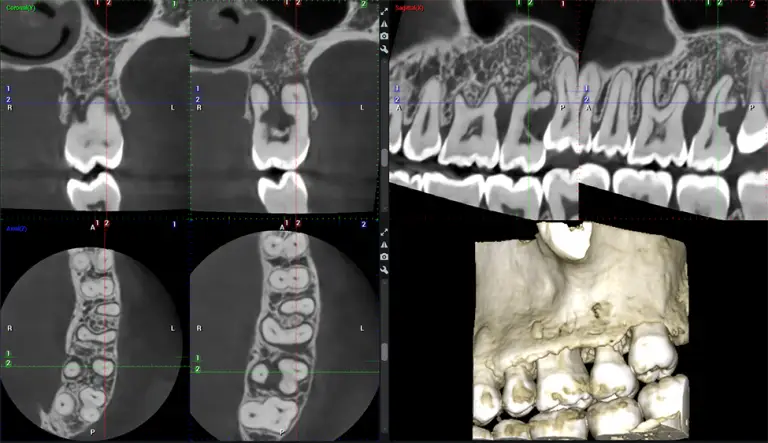

Dr. G Dental Studio is proud to welcome patients from Doral, FL. Our Miami office offers a full range of services for Doral residents — including cosmetic dentistry, dental implants, porcelain veneers, root canals, braces, wisdom tooth removal, and 3D CBCT imaging. Conveniently located just a short drive from Doral with easy parking and flexible appointment times. Call (305) 217-6453 to schedule your visit.